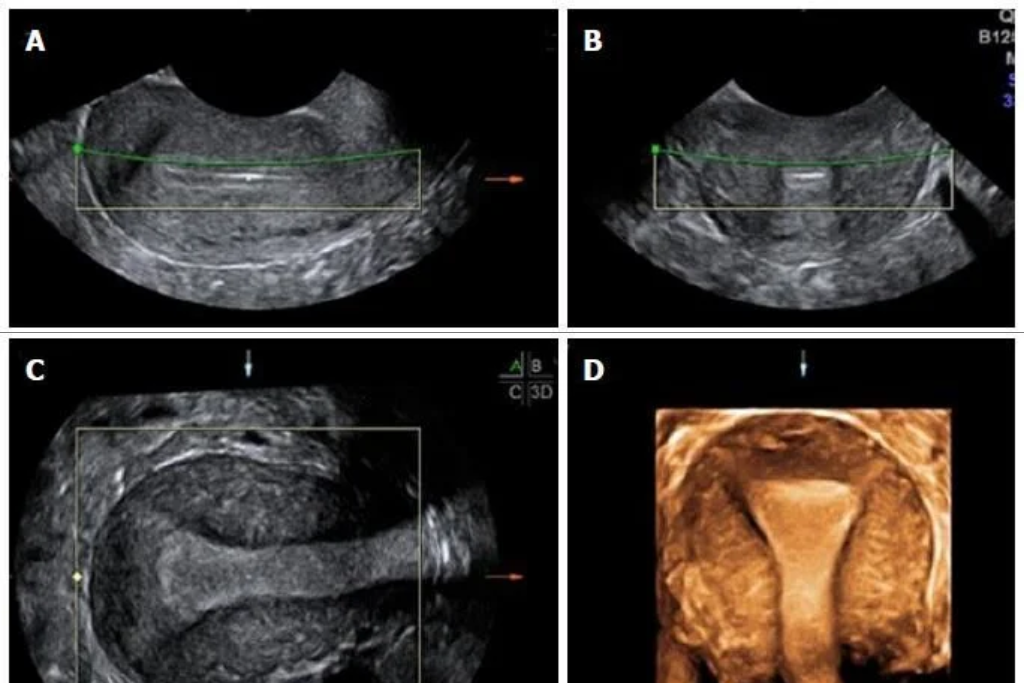

3D Ultrasonography

An advanced ultrasound that creates three-dimensional images for better detail and structure.

- Saline Infusion Sonography (SIS): A special procedure using saline to assess the uterine cavity for polyps or scars.

SIS (Saline Infusion Sonography)

An ultrasound in which saline is injected into the uterus to examine its inner lining clearly.